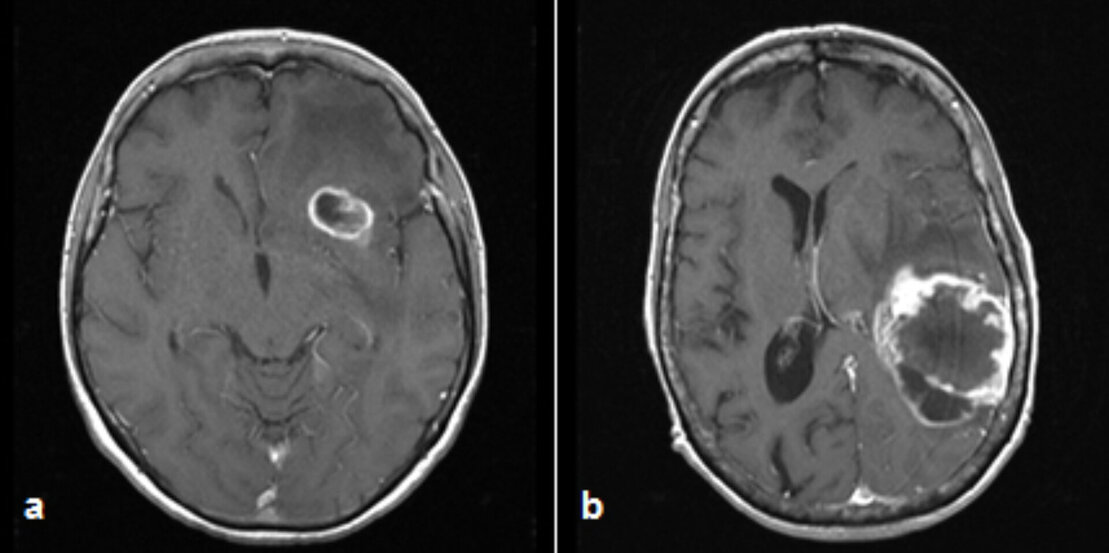

frontal links (a) und temporoparietal links (b)

Die Diagnostik erfolgt durch CT- und MRT-Bildgebungen. Diese Bilder können auch während der Operation zur Neuronavigation benutzt werden, um den Tumor und umliegende Hirnstrukturen genau lokalisieren zu können. Differenzialdiagnostisch können auch nuklearmedizinische Untersuchungen wie die PET (Positronen-Emissions-Tomographie) oder SPECT (Einzelphotonen-Emissionscomputertomographie) zur Anwendung kommen. Je nach Lokalisation können auch noch weitere präoperative Untersuchungen, wie z.B. die navigierte transkranielle Magnetstimulation (nTMS) oder das Diffusions-Tensor-Imaging Fibretracking (Traktographie) sinnvoll sein.